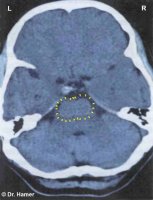

Tento sken mozku ukazuje Konstelaci SKL (viz diagram GNM), způsobenou dvěma Konflikty uprchlíka.